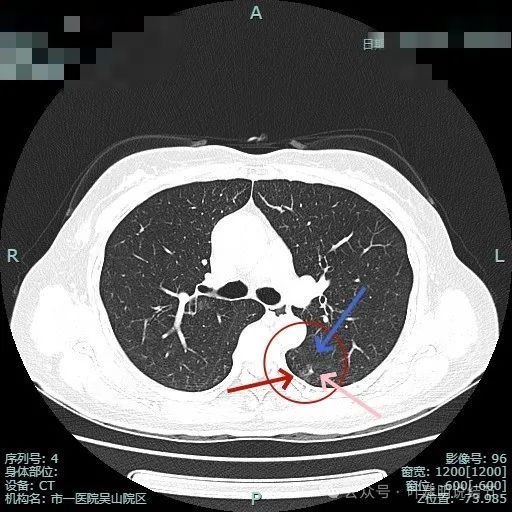

病灶1已经淡,且靠降主动脉近;病灶2密度其实也不纯,灶内有微小血管穿行,边缘侧有血管贴边,与支气管管壁间没有间隙。

病灶1边缘部分的样子;病灶表面欠光滑,有血管贴边。整体轮廓与边界清楚。